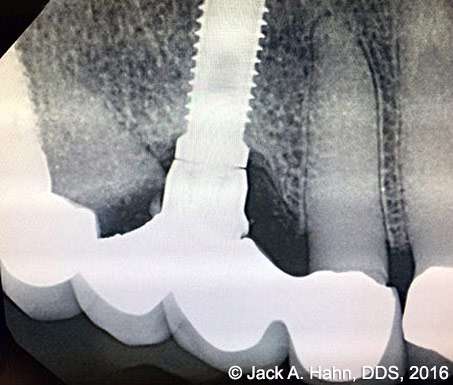

CASE #4 Trauma Case – Central Incisors Internal / External Resorption

Implants, that replace failed endo- or perio-compromised teeth, have a MUCH higher success rate with laser decontamination of the osteotomy site. LightScalpel laser surgical and perio laser tips ensure excellent access to extraction socket for the optimum removal of granulation tissue and socket decontamination (protocol involves manual curettage of the socket with alternating rinsing and lasing).

The patient, a 17-year-old female was involved in a water slide accident 3 years ago. As a result, both central incisors were avulsed and an endodontist replanted them. Both teeth exhibited internal and external resorption. Dr. Hahn extracted both central incisors, removed all the root fragments and sanitized the sites with the LightScalpel laser which also eliminated any granulation tissue. The #8 area was prepared to place a Hahn 4.3×13 Implant and #9 was prepared for a Hahn 3.5×13. 3mm tall Hahn healing abuts were placed slightly below the gingival-tissue level to help develop an emergence profile when at the restoration time in 4 months. Upon seeing the x-ray, Dr. Hahn tightened the healing abutment on #9 to be sure that it was completely seated on the implant. 45nucm. stability was achieved on both implants. He then placed some bone putty to seal any openings. To be on the safe side, he decided to place a temporary partial instead of immediate temporary prosthetics.